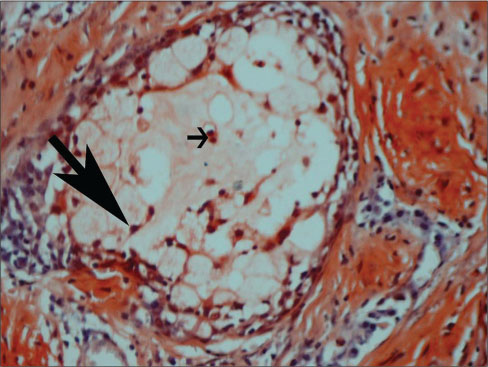

| Figure 2 Congo red staining in mucoepidermoid carcinoma Grade I (×100)-positively stained eosinophils